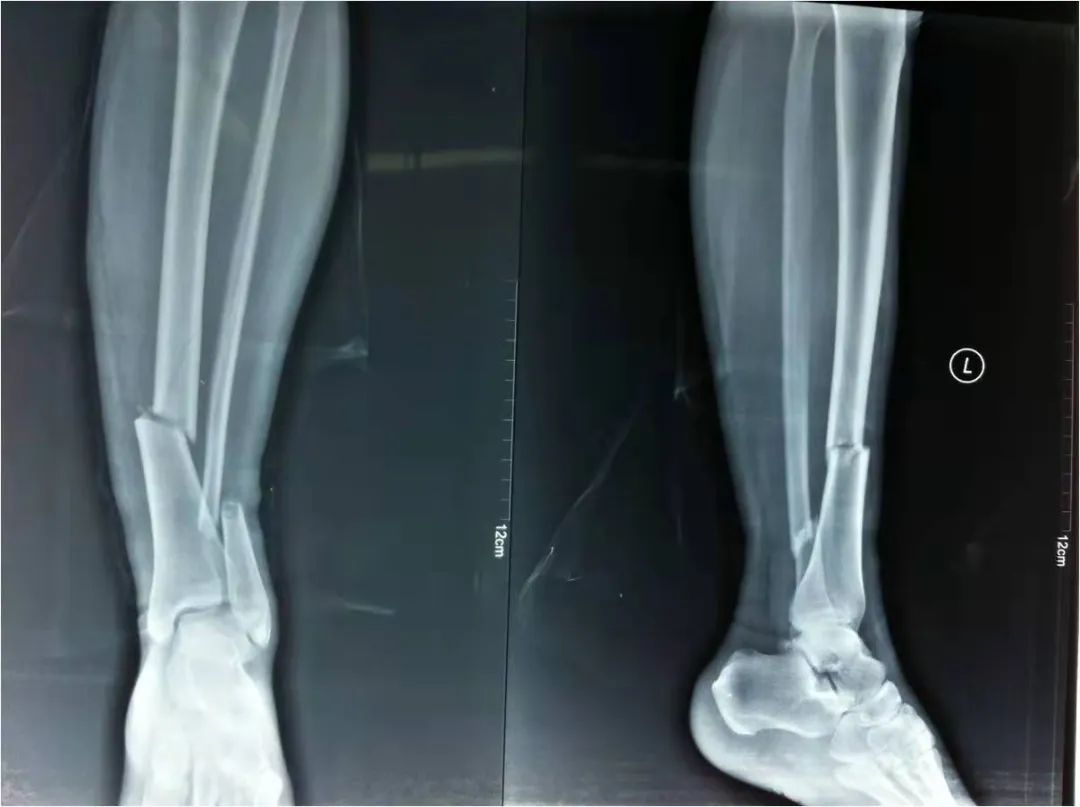

2022年4月22日,我院急救中心接診了一名骨折患者:患者在家不慎摔倒,導(dǎo)致剛做完手術(shù)沒(méi)多久的脛腓骨再次受創(chuàng),疼痛劇烈傷情加重。骨科呂國(guó)福主任迅速給予夾板外固定治療,并給予止疼治療減輕患者疼痛。經(jīng)診斷患者脛腓骨粉碎性骨折明確,且第一次接骨板釘?shù)廊钥梢?jiàn),如不及時(shí)手術(shù)可能出現(xiàn)骨斷端外露發(fā)展為開(kāi)放性骨折,可能出現(xiàn)骨筋膜室綜合癥。

如采用傳統(tǒng)手術(shù)需大范圍剝離軟組織,手術(shù)切口在18公分,損傷面大,影響骨折愈合。經(jīng)過(guò)科內(nèi)術(shù)前討論后與患者及家屬溝通后,呂國(guó)福主任決定行小切口微創(chuàng)鈦板植入內(nèi)固定手術(shù)治療,術(shù)中植入內(nèi)固定物并剝離軟組織,此方法對(duì)周?chē)つw破壞小,手術(shù)切口最小僅0.5公分,極大降低皮膚壞死及后期出現(xiàn)骨不連發(fā)生幾率,從而達(dá)到解剖復(fù)位。